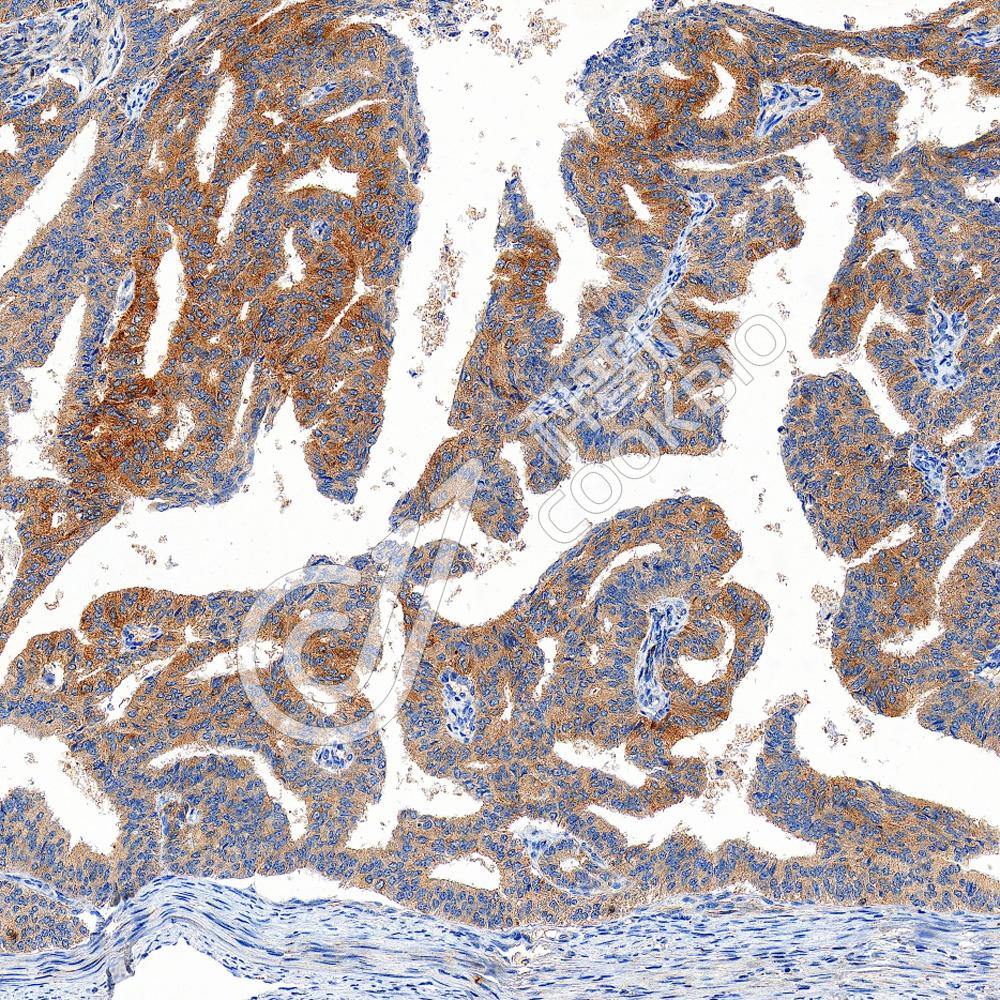

IHC检测Phospho-Tau(S202/T205)蛋白(货号 K5450180).

样品: 小鼠阿尔茨海默氏症脑模型, 4%多聚甲醛 (货号KSG1101) 固定12-24小时.

抗原修复: 柠檬酸抗原修复液(干粉, pH 6.0) (KSG1201), 高压锅均匀喷气计时2分钟.

—抗: 1: 300稀释, 4℃ 孵育过夜.

二抗: S-vision免疫组化多聚二抗(山羊抗兔),即用型 (货号KB3906), 室温孵育20分钟.